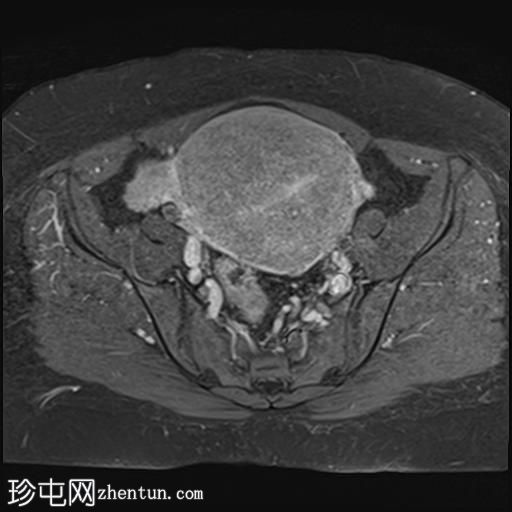

轴位T1加权像

增强脂肪抑制像

子宫增大,子宫内膜-肌层交界区弥漫性增厚,T1加权像呈中等信号,最高达45 mm;T2加权像呈低信号,内含多个小的高T2信号灶,提示月经出血渗入异位子宫内膜组织,符合弥漫性子宫腺肌症的

影像

学表现。

卵巢可见多个小的单房囊肿,无分隔或实性成分,最可能是浆液性包涵囊肿。

MRI表现最符合弥漫性子宫腺肌症。